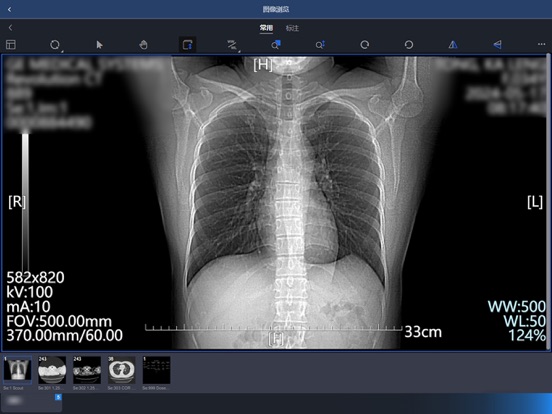

【产品说明】 东软睿影移动办公系统基于云计算和现代互联网技术,实现了各种影像数据和检查报告的云浏览,提供多种图像调整和测量功能,支持远程查看和编辑报告,使得医生可以在任意地点通过移动终端方便快捷的进行远程诊断。 【产品特性】 - 实现了包含放射、超声、内镜、病理、心电等在内的各类影像检查资料的云浏览,可随时随地浏览和诊断; - 采用身份认证机制,多种角色实现用户权限控制; - 支持多种条件查询患者检查信息,并可查看相关检查和申请单; - 多种操作模式,丰富的图像调整和测量功能; - 随时查看和编辑报告,同时支持输入模板,方便医生快速编写报告。 【联系我们】 微信公众号:东软HIT解决方案 客服电话:4006556789-7 官方网站:https://www.neusoft.com/cn1.修复多页报告无法查看的问题 2.增加token有效期自动登录